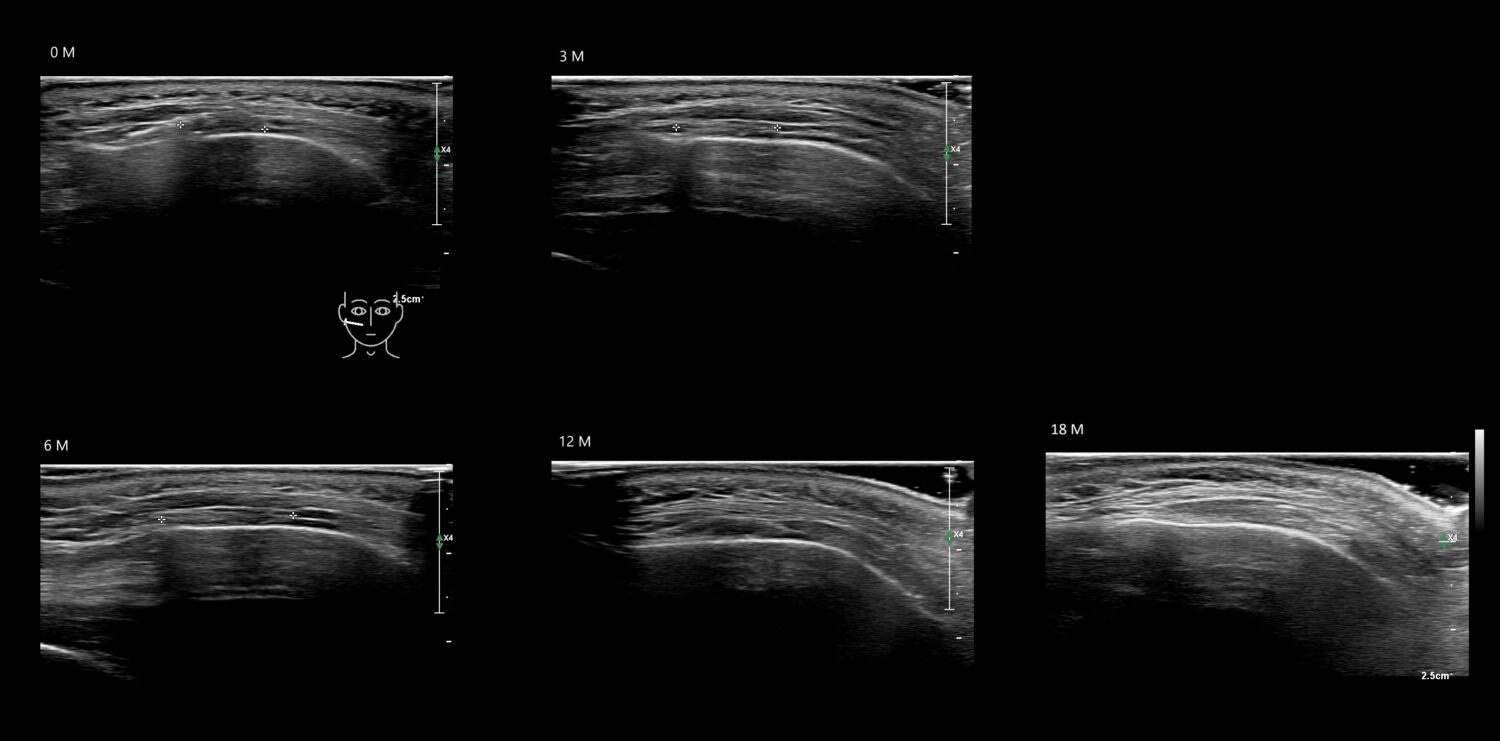

Filler library